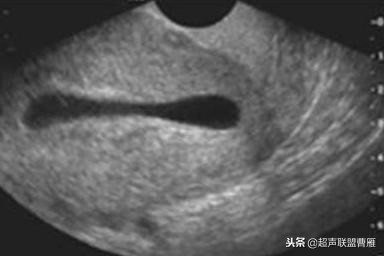

有的图像卵黄囊YS只是两条平行的细短线

妊娠37天超声检查卵黄囊可以显示,羊膜腔及胚胎不能显示

妊娠37天出现卵黄囊

在妊娠妊娠38天前后(36-40)天可以见到卵黄囊。 孕囊在6-9mm的可以见到其中有卵黄囊。